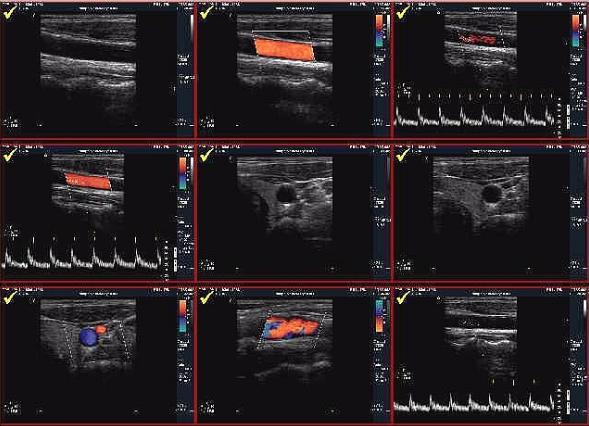

Техника проведения исследования

Выполняется она тем же способом, что и простое ультразвуковое исследование. Человек должен лечь на кушетку и занять удобное положение. Исследуемую часть тела освобождают от одежды. Длится процедура от 20 до 60 минут. УЗДГ БЦА может назначаться пациентам любого возраста.

Этот метод позволяет обнаружить различные патологии сосудистой системы воротниковой зоны. На ранних стадиях атеросклероза выявляются утолщения интима-медиа комплекса сонной артерии. При осмотре обнаруживаются холестериновые бляшки, оседающие на стенках сосудов. Определяется степень сужения и протяженность пораженного участка. При формировании бляшек артерия может подвергаться окклюзии (полной закупорке) или стенозу (частичному сужению просвета).

С помощью процедуры выявляется расслоение сосудов, называемое диссекцией. Утолщение стенок наводит врача на подозрение о синдроме Такаясу (неспецифическом аортоартериите). Патологические изменения, свойственные этому заболеванию, сложно отличить от признаков атеросклероза, поэтому врач должен внимательно изучать артерии. В ходе УЗДГ обнаруживается разность верхнего давления на плечах. В таком случае речь идет о закупорке одного из участков позвоночной артерии.

Расшифровка результатов выполняется неврологом или сосудистым хирургом. При отсутствии патологий артерии должны иметь прямолинейный ход, равномерную поверхность и стенки нормальной толщины. При наличии атеросклеротических бляшек в заключении указывается их состав, размеры и локализация. Отмечается их влияние на гемодинамику и степень сужения сосудов пораженных областей.

Измеренные в ходе допплерографии скорости кровотока сравниваются с нормативами. Таким же способом вычисляется пульсационный индекс и показатель устойчивости. Эти характеристики свидетельствуют о проходимости сосудов и степени их сопротивления. УЗДГ дает возможность выявить некоторые заболевания артерий головы и шеи, однако для установления точного диагноза требуется применение дополнительных методик.